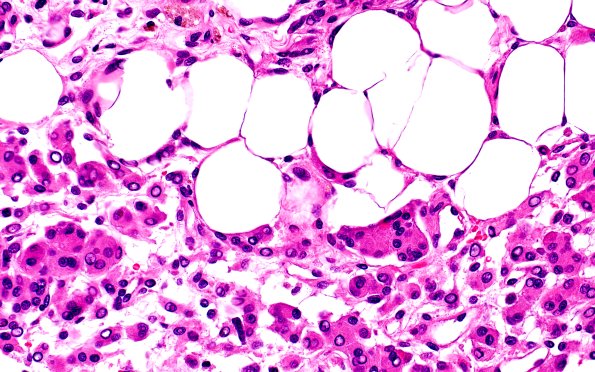

17C6Meningioma, lipidized (Case 17 60X 2

Higher magnification images show fat within tumor cells. (H&E)